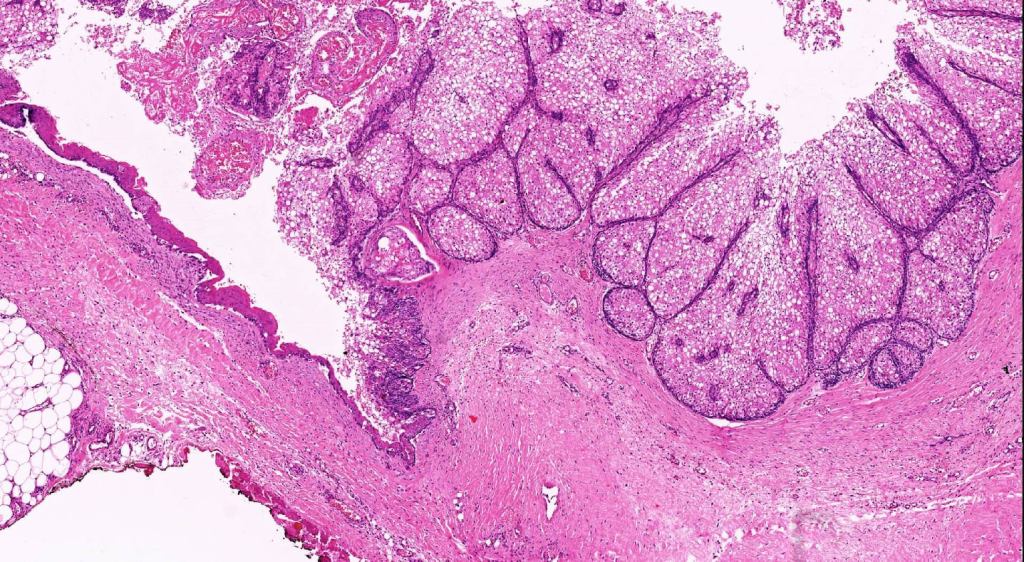

Histological features

•Variable continuity with epidermis

•Multinodular with surrounding collagenous stroma

•Random distribution of basaloid cells & sebocytes (<50% sebocytes)

•Duct formation, often with holocrine secretion generally present

•Mitoses sparse to conspicuous

•Absent peripheral palisading & retraction artifact